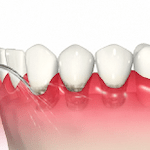

・スケーリング

スケーラーと呼ばれる器具を使用して、歯と歯の間や歯茎の上についている歯石(縁上歯石)を除去します。

・ルートプレーニング

歯茎の中や歯根表面にこびりついている歯石(縁下歯石)を除去し、歯根表面を滑らかに研磨して再び汚れがつきにくいようにします。